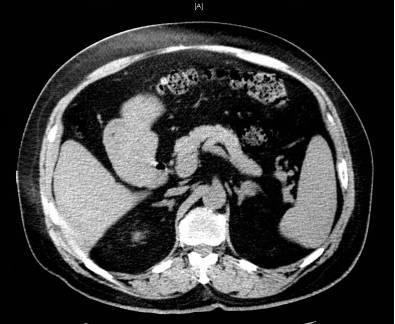

肾上腺CT(2017年9月)

左侧肾上腺占位,左肾上腺外肢类圆形等密度病变约2.0 ㎝×1.7 ㎝,考虑腺瘤可能,较2013年4月7日CT结果,无显著改变(图3)。

图3